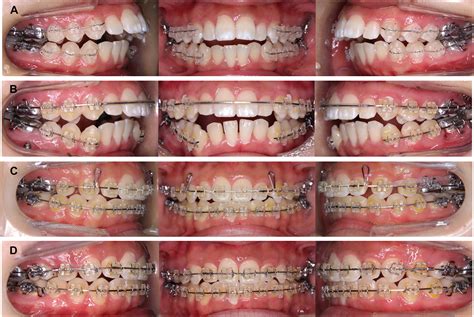

• Orthognathic Surgery: Once the condition has been deemed "stable" (the resorption has stopped), jaw surgery may be performed to correct the bite and facial structure.

One of the most critical aspects of treatment is timing. If a surgeon performs corrective surgery while the resorption is still active, there is a high risk that the new jaw position will not be maintained, and the bone will continue to resorb post-operatively. Therefore, proving clinical stability through serial imaging is a mandatory precursor to any surgical intervention.